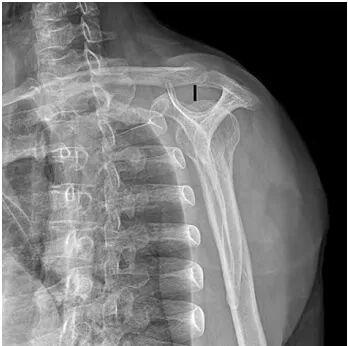

X线检查:X线可清晰显示骨骼结构、钙化及骨赘等,主要包括肩关节前后正位及冈上肌出口位,可观察临界肩角(CSA)、肩肱指数(AI)、肩峰形态、肩峰肱骨头间距(ADH )等。

该肩关节冈上肌出口位X线片 显 示 为Ⅲ型肩峰 (A-H 间距为 9 mm,提示肩峰下间隙狭窄)